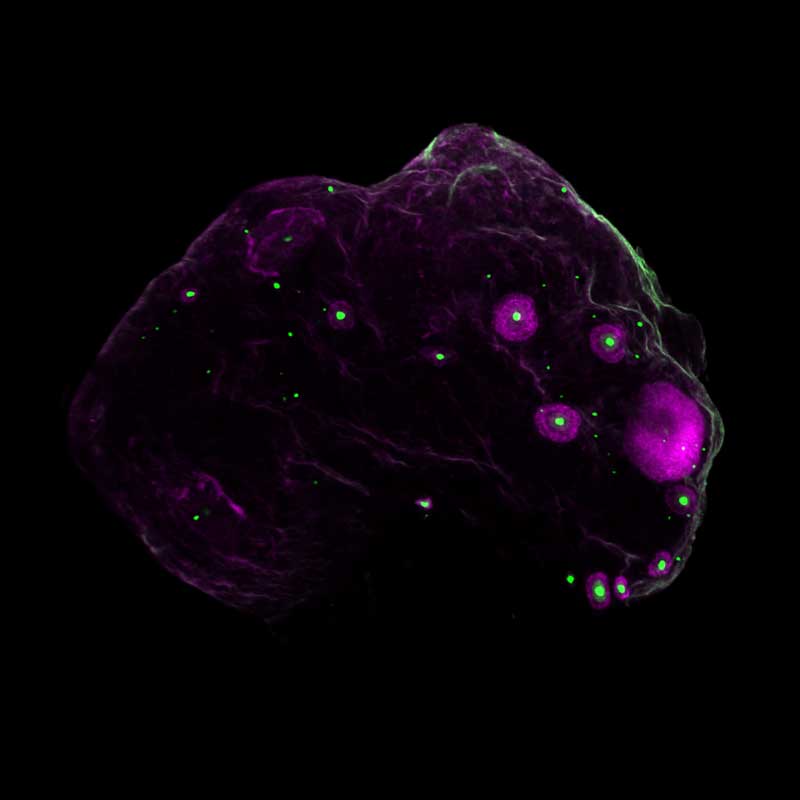

A 3D view of a whole mouse ovary, with every egg marked in green and the growing egg follicles in magenta.

The number of eggs (green) decline with age. Growing eggs are shown in magenta. At left is a 2-month-old mouse. At right is a 12-month-old mouse. Images by Gaylord, et al.

In mice that were the equivalent of 30 to 40 human years, they observed a dramatic drop in both immature resting eggs that are waiting in reserve and in growing eggs that are beginning to mature for ovulation. And just like women in their 30s, the mice did not conceive easily with in vitro fertilization (IVF).

When the scientists extended their 3D imaging to human ovaries, they uncovered an unexpected finding: Eggs are not evenly scattered throughout the ovary. Instead, they cluster in “pockets” surrounded by egg-free zones. With age, the density of eggs within these pockets declines.